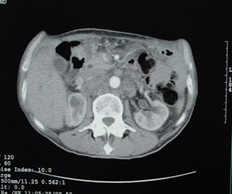

女,40岁,2006年10月底确诊为胃腺癌(皮革胃),腹腔淋巴结转移;2006年11月外科手术时见腹腔广泛转移(粘连),病灶无法切除(下图1a,b),预期生存期低于3个月;留置(胃)造瘘管。2006年12月开始今又生联合化疗治疗,今又生2×1012VP,室温下自行融化后加入到100ml生理盐水中,30~40分钟内静脉滴注完毕,1/次/周,连续使用6周。今又生给药三天后静脉化疗。2007年7月外科手术拔除造瘘管;2007年9月随访,患者状况良好,无复发。

1a 治疗前胰腺体部和主动脉前方淋巴结较多较大,胃底和体部较厚僵硬

1b治疗后 淋巴结较少并缩小,胰腺和主动脉之间脂肪间隙恢复清晰,胃底和体部较前变薄,柔软